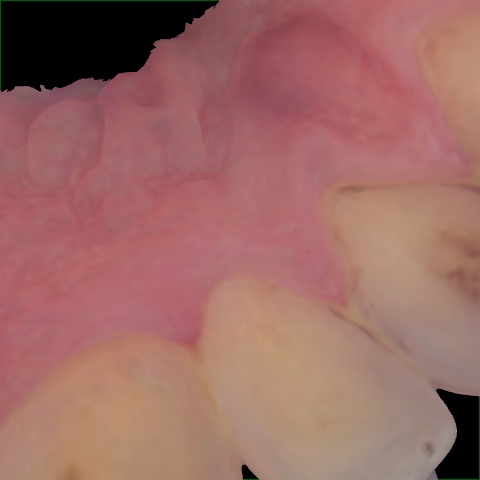

Annotated as "Good"